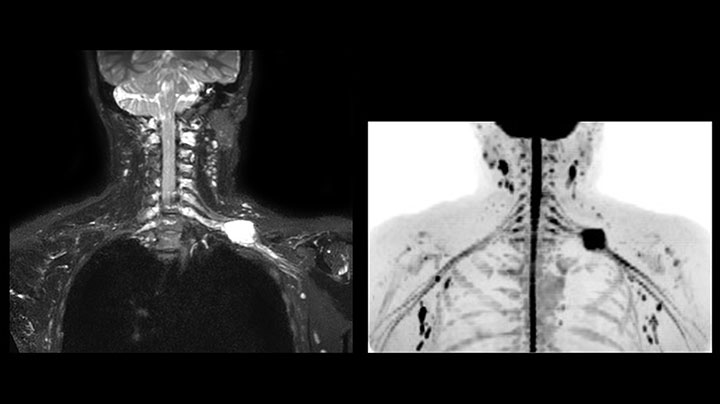

Although the area between the neck and the top of the lung is one of the most difficult areas for MRI, Prodiva 1.5T images show good quality in this 56-year-old male with Pancoast tumor on the right. mDIXON TFE images shows excellent fat suppression in the neck area and the DWI shows almost no distortion.

Acq voxel size 1.2 x 1.3 x 2.4 mm, Recon voxel size 0.7 x 0.7 x 1.2 mm, dS SENSE factor 2, scan time 5:46 min.